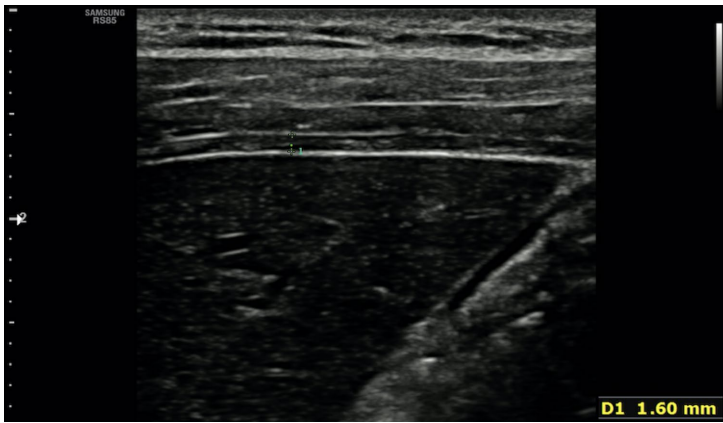

研究采用随机对照设计,创新性地将PowerBreathe吸气肌训练设备整合到跑步机步行中,形成"步行特异性吸气肌训练(W-SIMT)"方案。关键技术包括:1) 使用剪切波弹性成像(SWE)定量评估膈肌厚度与刚度;2) 通过功率自行车测试(RAST)分析无氧运动表现;3) 采用增量阈值负荷试验测定呼吸肌耐力参数(Pmax, Tmax);4) 标准化肺功能测试(FEV1/FVC等)监测呼吸功能变化。

膈肌结构与功能:超声检测显示两组膈肌吸气相厚度均增加,W-SIMT组提升20.9%,但组间差异未达显著水平。剪切波弹性成像首次揭示膈肌吸气相刚度始终高于呼气相。